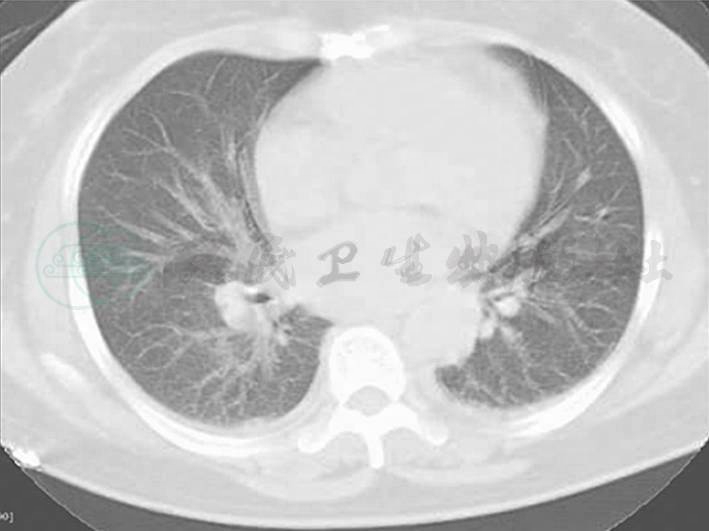

图1 胸腹部CT

两肺纹理增多增粗,两下肺背侧见斑片高密度影,边界模糊;两侧少量胸腔积液(7月8日)